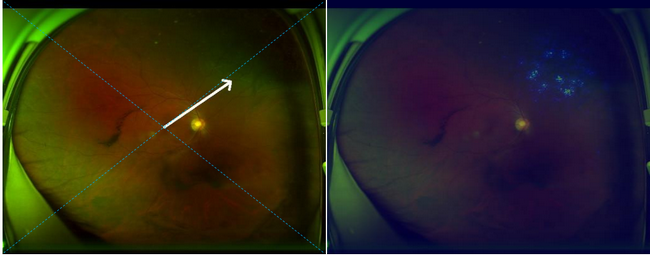

左側圖片箭頭指處為視網膜脫離,右側圖片高亮區域熱圖提示視網膜脫離的精確位置

這款系統不僅能對眼底圖像進行解讀,同時可以自動標出病變部位,有助于醫生有針對性的解讀報告。同時如果視網膜脫離檢查結果呈陽性,系統會自動給予體位指導,以延緩視網膜脫離的進展,降低手術并發癥,改善患者的視力預后。